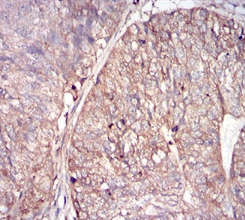

IHC    1/200 - 1/1000